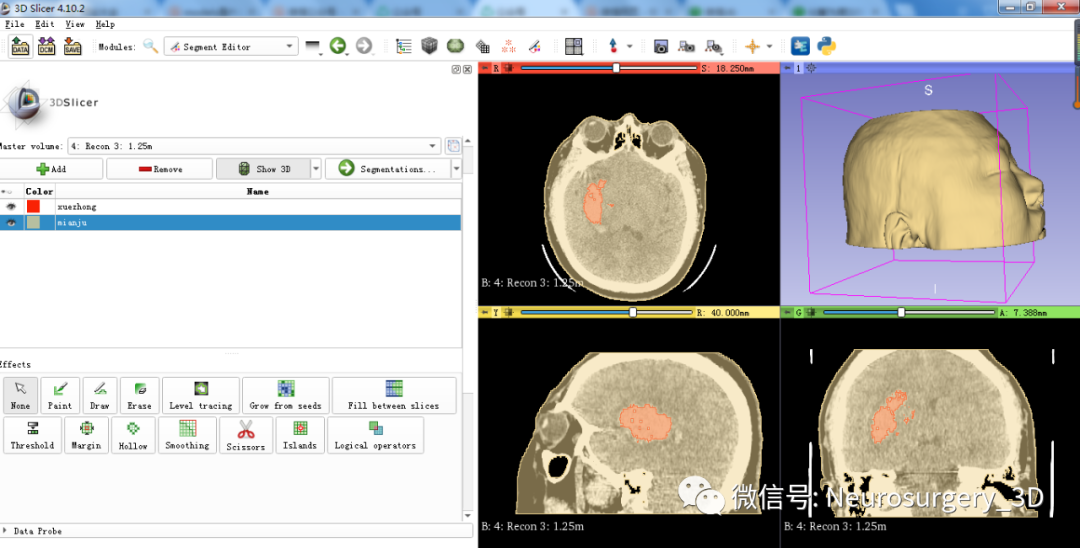

二)利用Logical operators逻辑运算模块的复制、相减功能生成面具模型

1、同阈值分割法建立血肿,应用阈值分割法三维重建头颅原始模型

2、可透视化显示颅内血肿形态

3、利用Logical operators逻辑运算模块复制头颅原始模型并扩大。